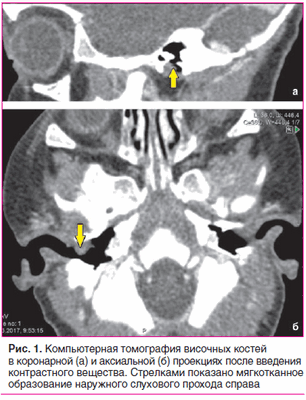

После угасания острого воспалительного процесса наружного слухового прохода справа выполнена компьютерная томография височных костей с внутривенным введением контрастного вещества.

С целью уточнения распространенности процесса назначена компьютерная томография височных костей с внутривенным введением контрастного вещества.

По данным компьютерной томографии височных костей, выполненной по стандартной программе до и после внутривенного введения контрастного вещества, на задней стенке наружного слухового прохода справа определяется мягкотканное образование однородной структуры, овальной формы с четкими контурами, размером 7×5,5 мм. Образование прилежит к барабанной перепонке, несколько смещает ее внутрь, умеренно накапливает контрастный препарат. Просвет наружного слухового прохода в данной области сужен до 1 мм. Костных деструктивных изменений не выявлено. Антрум и барабанные полости с обеих сторон пневматизированы. Слуховые косточки прослеживаются четко. Улитки без особенностей (рис. 1).